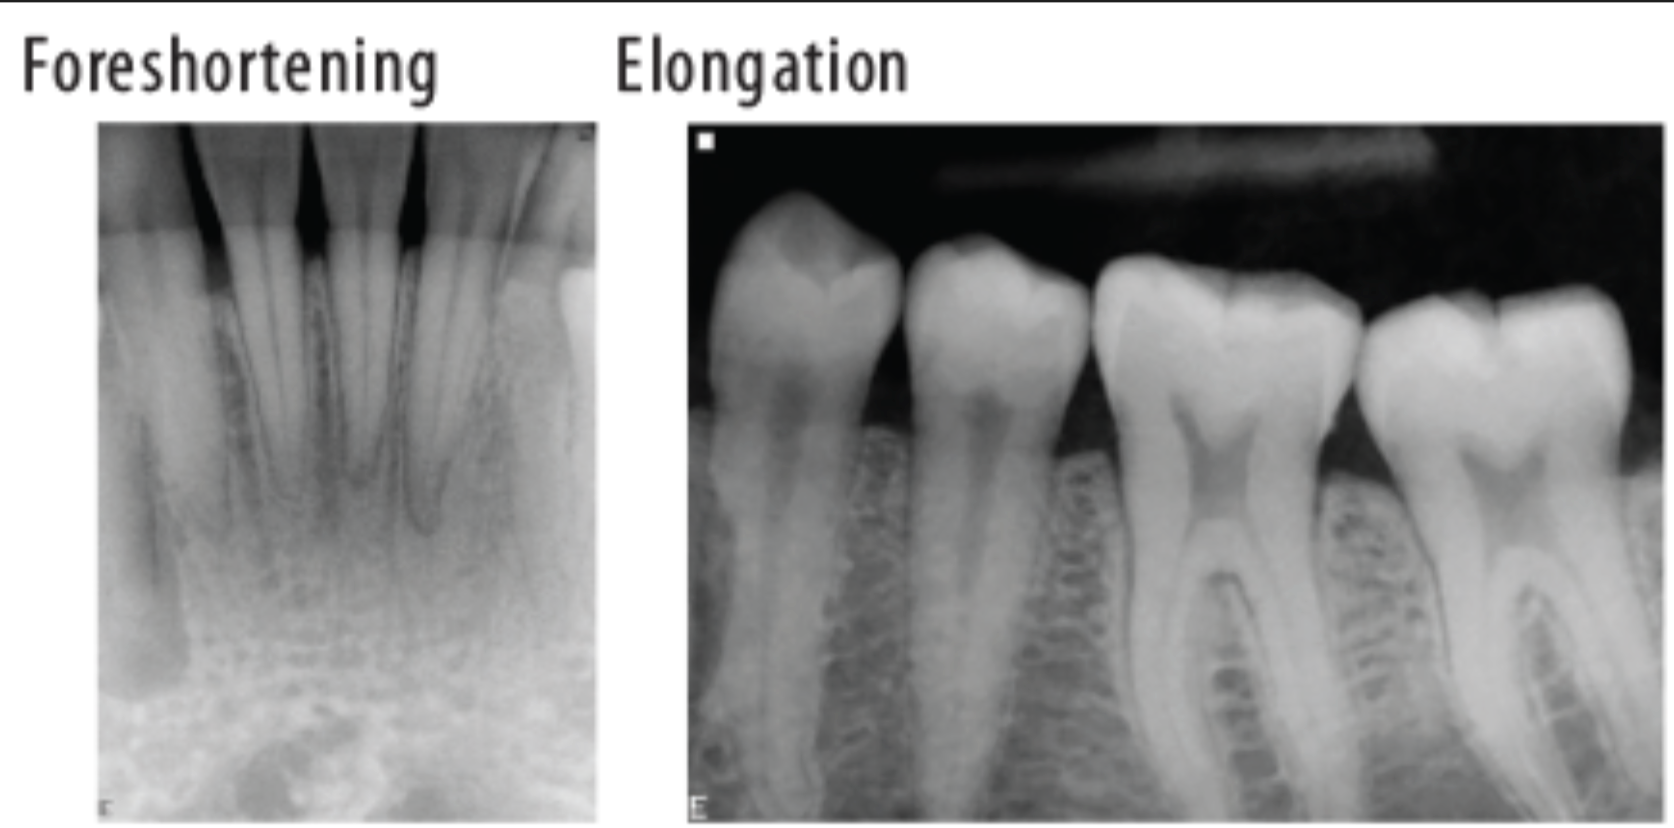

What is foreshortening the roots?

It means we have an excessive angulation which shortens the roots and elongates the crown.

Foreshortening= excessive vertical angulation

Elongation= insufficient vertical angulation

What leads to elongation in a radiograph?

When there is insufficient angulation when taking a maxillary or mandibular photo.